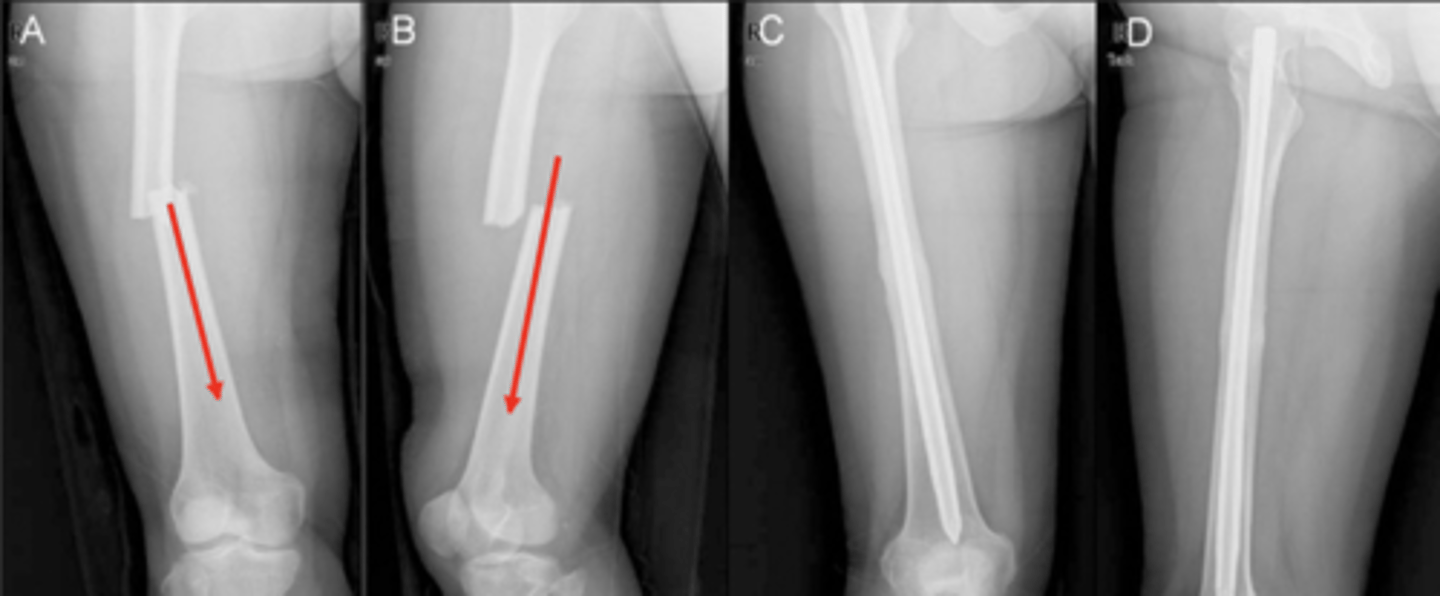

What does good position, good alignment look like vs. displaced with deviated alignment?

See image.

Name displacement based on the ________ fracture end in anatomical position

DISTAL!! -- i.e., "displaced medial, posterior, and overriding"

Name deviation based on the ________ bone angle in the ________ direction

DISTAL!! -- i.e., "deviated medial and anterior"